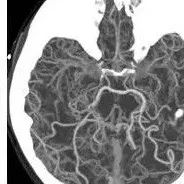

烟雾病和烟雾综合征

*仅供医学专业人士阅读参考烟雾病影像表现 本文首发:徐医附院影像科责任编辑:孙颖版权申明 本文转载 欢迎转发朋友圈- End -*医学界力求其发表内容在审核通过时的准确可靠,但并不对已发表内容的适时性,以及所引用资料(如有)的准确性和完整性等作出任何承诺和保证,亦不承担因该些内容已过时、所引用资料可能的不准确或不完整等情况引起的任何责任。请相关各方在采用或者以此作为决策依据时另行核查。...